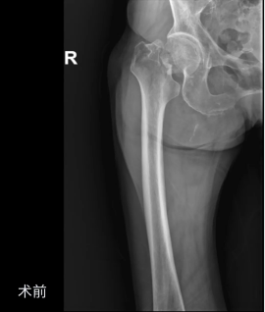

【省级专家就在家门口】82岁认知障碍老人骨折后重获站立,这场救治太暖了!

对于年过八旬、患有阿尔茨海默病的老人来说,世界或许早已模糊,但疼痛却异常清晰。一次不经意的摔倒,脆弱的髋部发生骨折,剧痛与恐惧便会瞬间将他们淹没——这不仅是骨科急症,更是一场可能加速认知衰退、导致长期卧床甚至危及生命的挑战。而面对认知障碍的高龄患者,手术的风险与保守治疗的困境,往往让家属和医生陷入“做与不做”的两难。

近日,我院骨科在南方医科大学附属第三医院(广东省骨科医院)派驻专家、骨科学科带头人胡舒主任的指导下,以不放弃的医者初心和精准的微创技术,成功

为82岁的中度阿尔茨海默病患者刘奶奶(化名)实施人工股骨头置换术

,不仅精准治疗骨折,更以最小创伤降低术后关节脱位风险,为她留住了早期下床、回归熟悉生活的希望。

刘奶奶在家中不慎跌倒,导致右侧股骨颈骨折。对于高龄老人,这被称之为“人生最后一次骨折”,保守治疗死亡率极高。

人工股骨头置换术是治疗这类患者的最优选择。